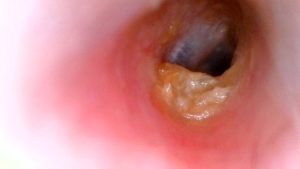

2. 외이도염 : 외이도(귓바퀴에서 고막에 이르는 통로)에 여러 가지 원인으로 세균이나 곰팡이 등에 감염되어 염증이 생기는 질환